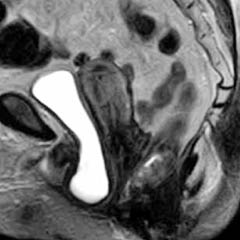

|

![]() |

Bladder

and Uterus in Pelvic Floor Dysfunction (PFD) |